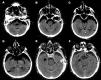

Coma due to tension pneumocephalus in the posterior fossae

Coma secundario a neumoencéfalo a tensión en fosa posterior